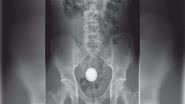

"Os médicos chegaram e me disseram que minha 'pedra renal' era na verdade um bebê de 37 semanas”, contou a mulher

Quando percebeu que não conseguiria tirar o objeto sozinho, o jovem contou para a mãe, que o levou para o pronto-socorro mais próximo